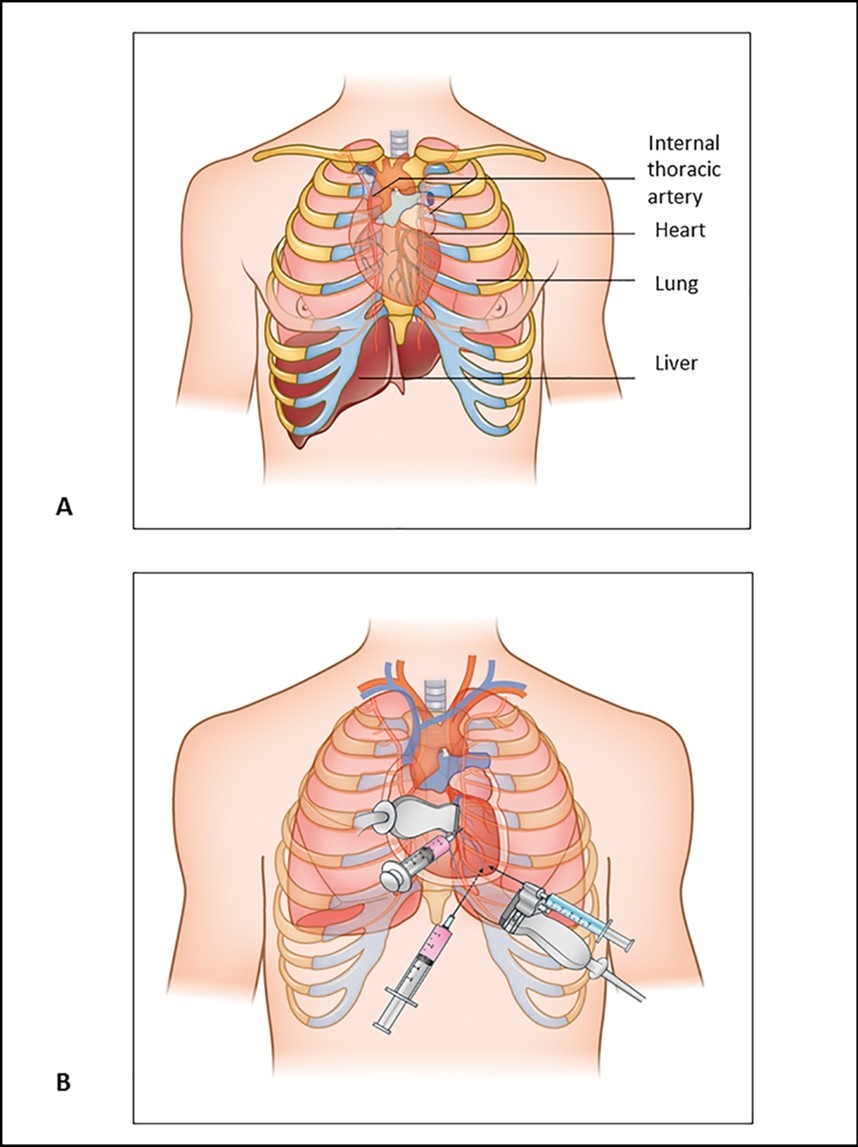

Pericardiocentesis: Anatomic structures and approaches are as follows, the pericardium is composed of visceral and parietal components. The pericardial space is enclosed between these two serosal layers and normally contains up to 50 mL of plasma ultra-filtrate, the pericardial fluid 8. The approach of pericardiocentesis should be held by the hands of an experienced operator because of the surrounding relations (Figure 2). Anteriorly, the fibrous pericardium is separated from the thoracic wall by the lungs and the pleural coverings. The direct contact of the pericardium with the thoracic wall is observed in a small area behind the lower left half of the body of the sternum and the sternal ends of left fourth and fifth costal cartilages.

Figure 2.Anatomic structures to be taken care during pericardiocentesis procedure.

The principal bronchi, oesophagus, oesophageal plexus, descending thoracic aorta and posterior parts of the mediastinal surface of both lungs are posterior relations. Laterally, the pleural coverings of the mediastinal surface of the lungs 14. The most commonly employed approach to closed pericardiocentesis is subxiphoid needle insertion 8 in the left fifth or sixth intercostals space near the sternum 14 directed towards the right shoulder. Approach should be done with echocardiographic guidance to minimize the risk of myocardial puncture and to assess completeness of fluid removal 15. Once the needle has entered the pericardial space, a modest amount of fluid should be immediately removed (perhaps 50 to 150 mL) in an effort to produce immediate hemodynamic improvement. A guidewireis then inserted and the needle replaced with a pigtail catheter under echocardiographic guidance to maximum fluid removal 8. ‘The bare area’ of the pericardium formed by the cardiac notch of the left lung and the shallow notch in the left pleural sac makes an easy approach to the pericardial sac. The pericardial sac can be approached through the infrasternal angle i.e; the left costo-xiphoid angle by passing the needle superoposteriorly or up and backwards in to the pericardial sac 16 at an angle of 45 degrees to the skin 17. At this site, the needle avoids the lung and pleurae and enters the pericardial cavity however; care must be taken not to puncture the internal thoracic artery. One of the more difficult management decisions is whether to perform closed verses open pericardiocentesis in patients with known or suspected bleeding in to the pericardial space. In minimised 16. [Figure 3A & B]

Figure 3.A. Anatomic structures to be taken care during pericardiocentesis procedure. B. Three main approaches for pericardiocentesis; a) Parasternal, b) Apical and c) Substernal

When the procedure is performed, the pleura and lung are not injured because of the presence of the cardiac notch in this area 16. The phrenic nerve, with its accompanying vessels, descends between the fibrous pericardium and mediastinal pleura on each side. Inferiorly, the pericardium is separated by the diaphragm from the liver and fundus of the stomach 14 (Figure 1).Ribs and their counting is done from the second costal cartilage is identified first at the level of sterna angle; thereafter the ribs are palpated and counted downwards and laterally away from the sternum in order to avoid confusion due to crowding of the cartilages of fifth, sixth and seventh ribs as they approach the sternum. The sterna end of the first rib can be felt immediately below the sternal end of the clavicle.